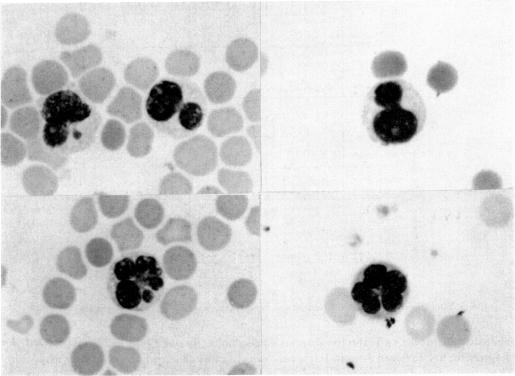

Several immunological tests were performed on eighty-five patients with rubella. There was a decrease in total leucocytes, neutrophils and T cells, an increase in IgG and the complement components of C4, C9 and CH50, and a marked insensitivity to dinitrochlorobenzen (DNCB) and purified protein derivative (PPD) in many patients. Furthermore, atypical lymphocytes with lobulated nuclei, autoantibodies and reduced blastogenesis were found in some patients. These abnormal findings disappeared within 1 month. These marked immune abnormalities, although transient, may indicate an inhibition of DNA synthesis in lymphocytes which may have some bearing on the high incidence of embryopathy in pregnant women.